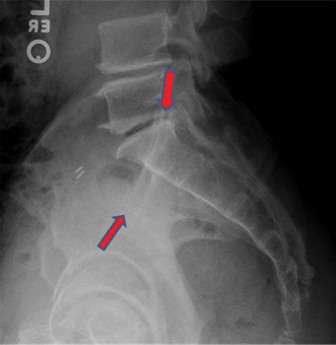

A 24-year-old male presents following a motor vehicle collision. His primary complaint is of lower back pain.…